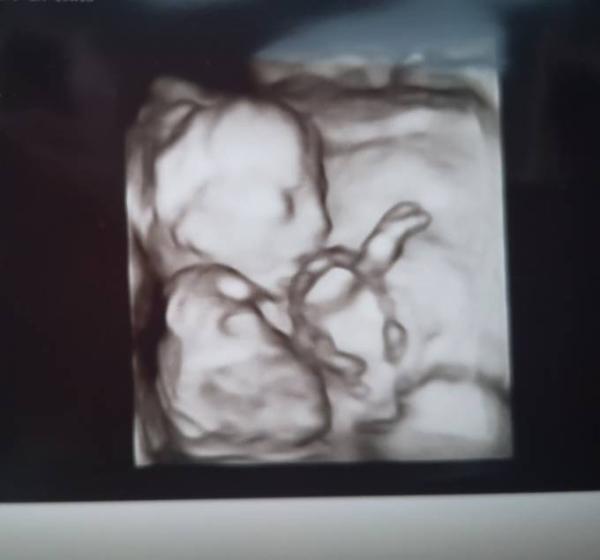

Wie vorhin ja berichtet war ich auf dem Weg zur VU und was soll ich euch sagen, ich bin unfassbar verliebt. Es gab ein Outing (was ich ja wie gesagt am Mittwoch erst erfahre) allerdings hat mein Fa mir glaube etwas meine Tendenz genommen und ich schätze das ich mich irre Ansonsten war mein Haribo unglaublich agil und hat sich immer vor dem Ultraschalkgerät versucht zu verstecken. Es ist dennoch ein wundervolles Bild entstanden Jetzt heisst es wieder 3 Wochen und 2 Tage abwarten, aber die Zeit rennt total davon finde ich

Bild zu Haribo TV, Outing und Bild 🥰 - Forum für Juli - Mamis